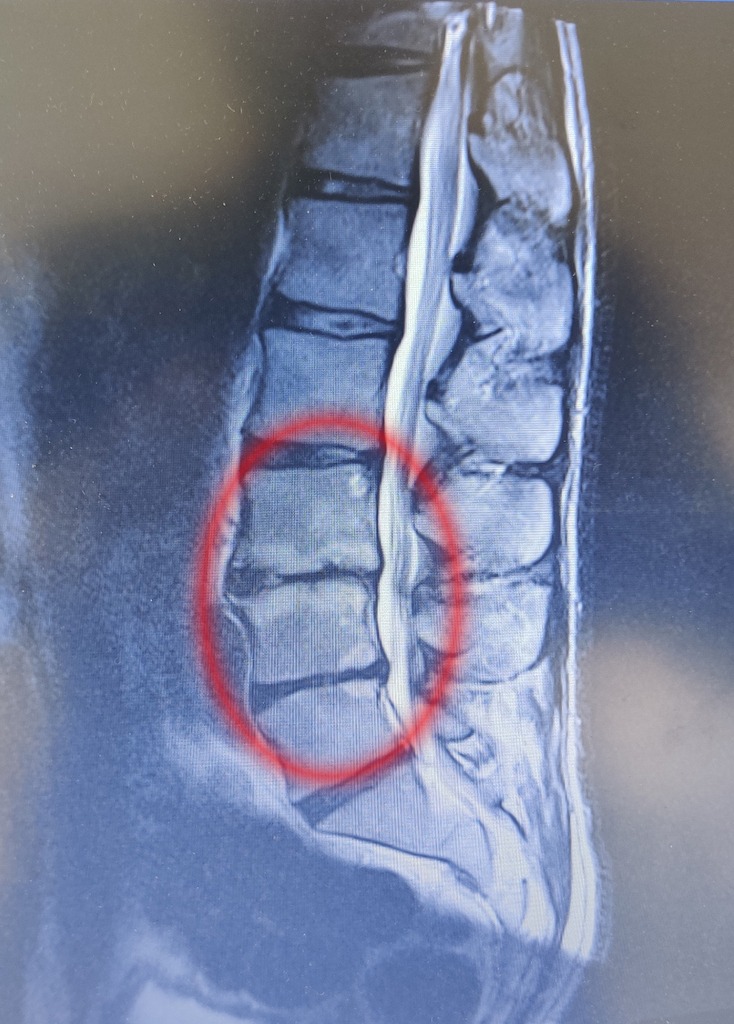

“As I was sorting through some of our old things, I came across an old MRI scan of my lower back when I was in my first year of chiropractic school, at the ripe old age of 27 (I’m now nearly 50!). I’d had previous surgery at L5/S1 when I was 23 and suffered back flare ups on and off since then, but this one was bad.

If you take a look at my scan (red circle), you can see multiple disc bulges, inflammation of the vertebrae, a narrow spinal canal and degenerative (or so-called “crumbling”) discs.

I was suffering quite severe back and leg pain at the time, and I can still remember being told that I had the “spine of a 65 year old” by one of the doctors. Great, thanks. I was really quite worried. How would I cope with the pain? When will it stop? How will I live with this for the rest of my life?

Compare the above image to this MRI of a healthy 20 year old lower back. It has lovely alignment, healthy vertebrae and discs, and a nice spacious spinal canal. You can see, based on my scan alone, how it would have been easy to give up hope and let the pain and fear set in. And let it control my life.

But I chose not too. Thanks to my experience and training as a chiropractor over the last 20 years, and my neuro-mechanical nutrition training, at the age of nearly 50 I am stronger than I’ve ever been. I can ride mountain bikes down scary hills (that’s me in the main pic), squat my own bodyweight, and deadlift twice my own bodyweight. Sure, I get the occasional flare up (the degeneration hasn’t gone anywhere!), but it is extremely rare and when it happens I know how to manage it. And I can help you to do that too!“